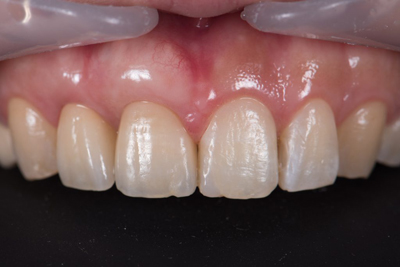

治療後

治療終了後

歯の根が溶けていて、右上の前歯の歯が残せない状態です。 前歯の審美的な不良も認めます。